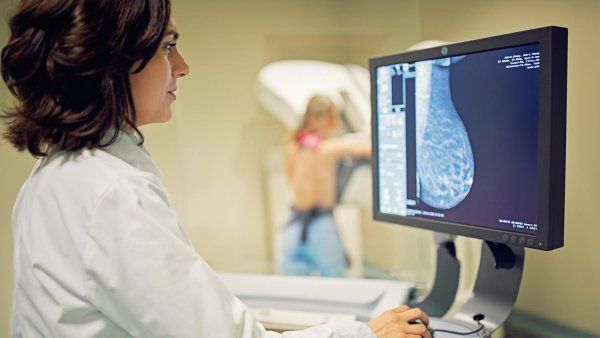

A study finds personalized breast cancer screening based on risk reduces advanced cancers and ensures safe, tailored mammogram frequency.

UCSF researchers found that regular screening is not always sufficient to prevent an advanced breast cancer diagnosis.

Laws in many states require notifying women if they have dense breasts, a risk factor for breast cancer. But density shouldn’t be the only factor in determining whether supplemental screening is

A new digital tool helps to calculate breast cancer risk for those who may develop advanced cancer that goes undiagnosed despite regular screenings.